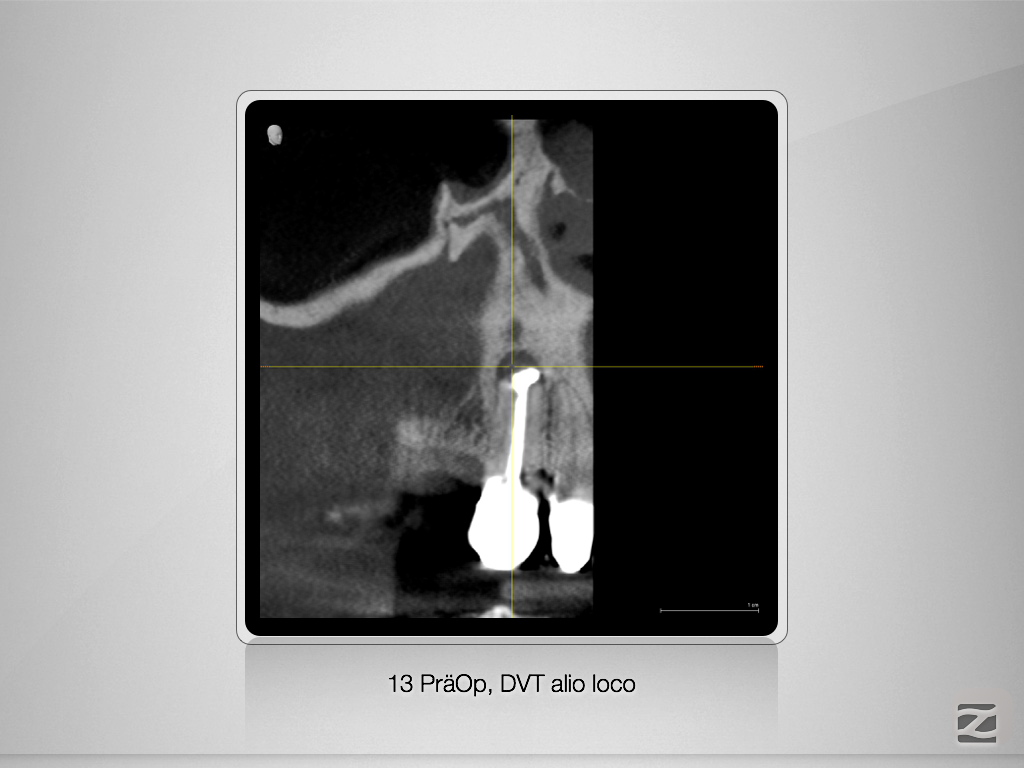

13D.002

Ketac Silver retrograd